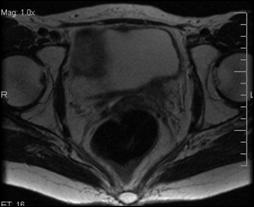

2. Diagnosticul diferential cu ureterocel bilateral